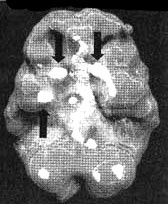

Мозг Брайса. Эпилепсия височных долей

Трехмерное изображение нижней поверхности. Обратите внимание на область повышенной активности в глубоких отделах правой височной доли (стрелка снизу вверх) и базальных ганглиях (стрелки вниз).